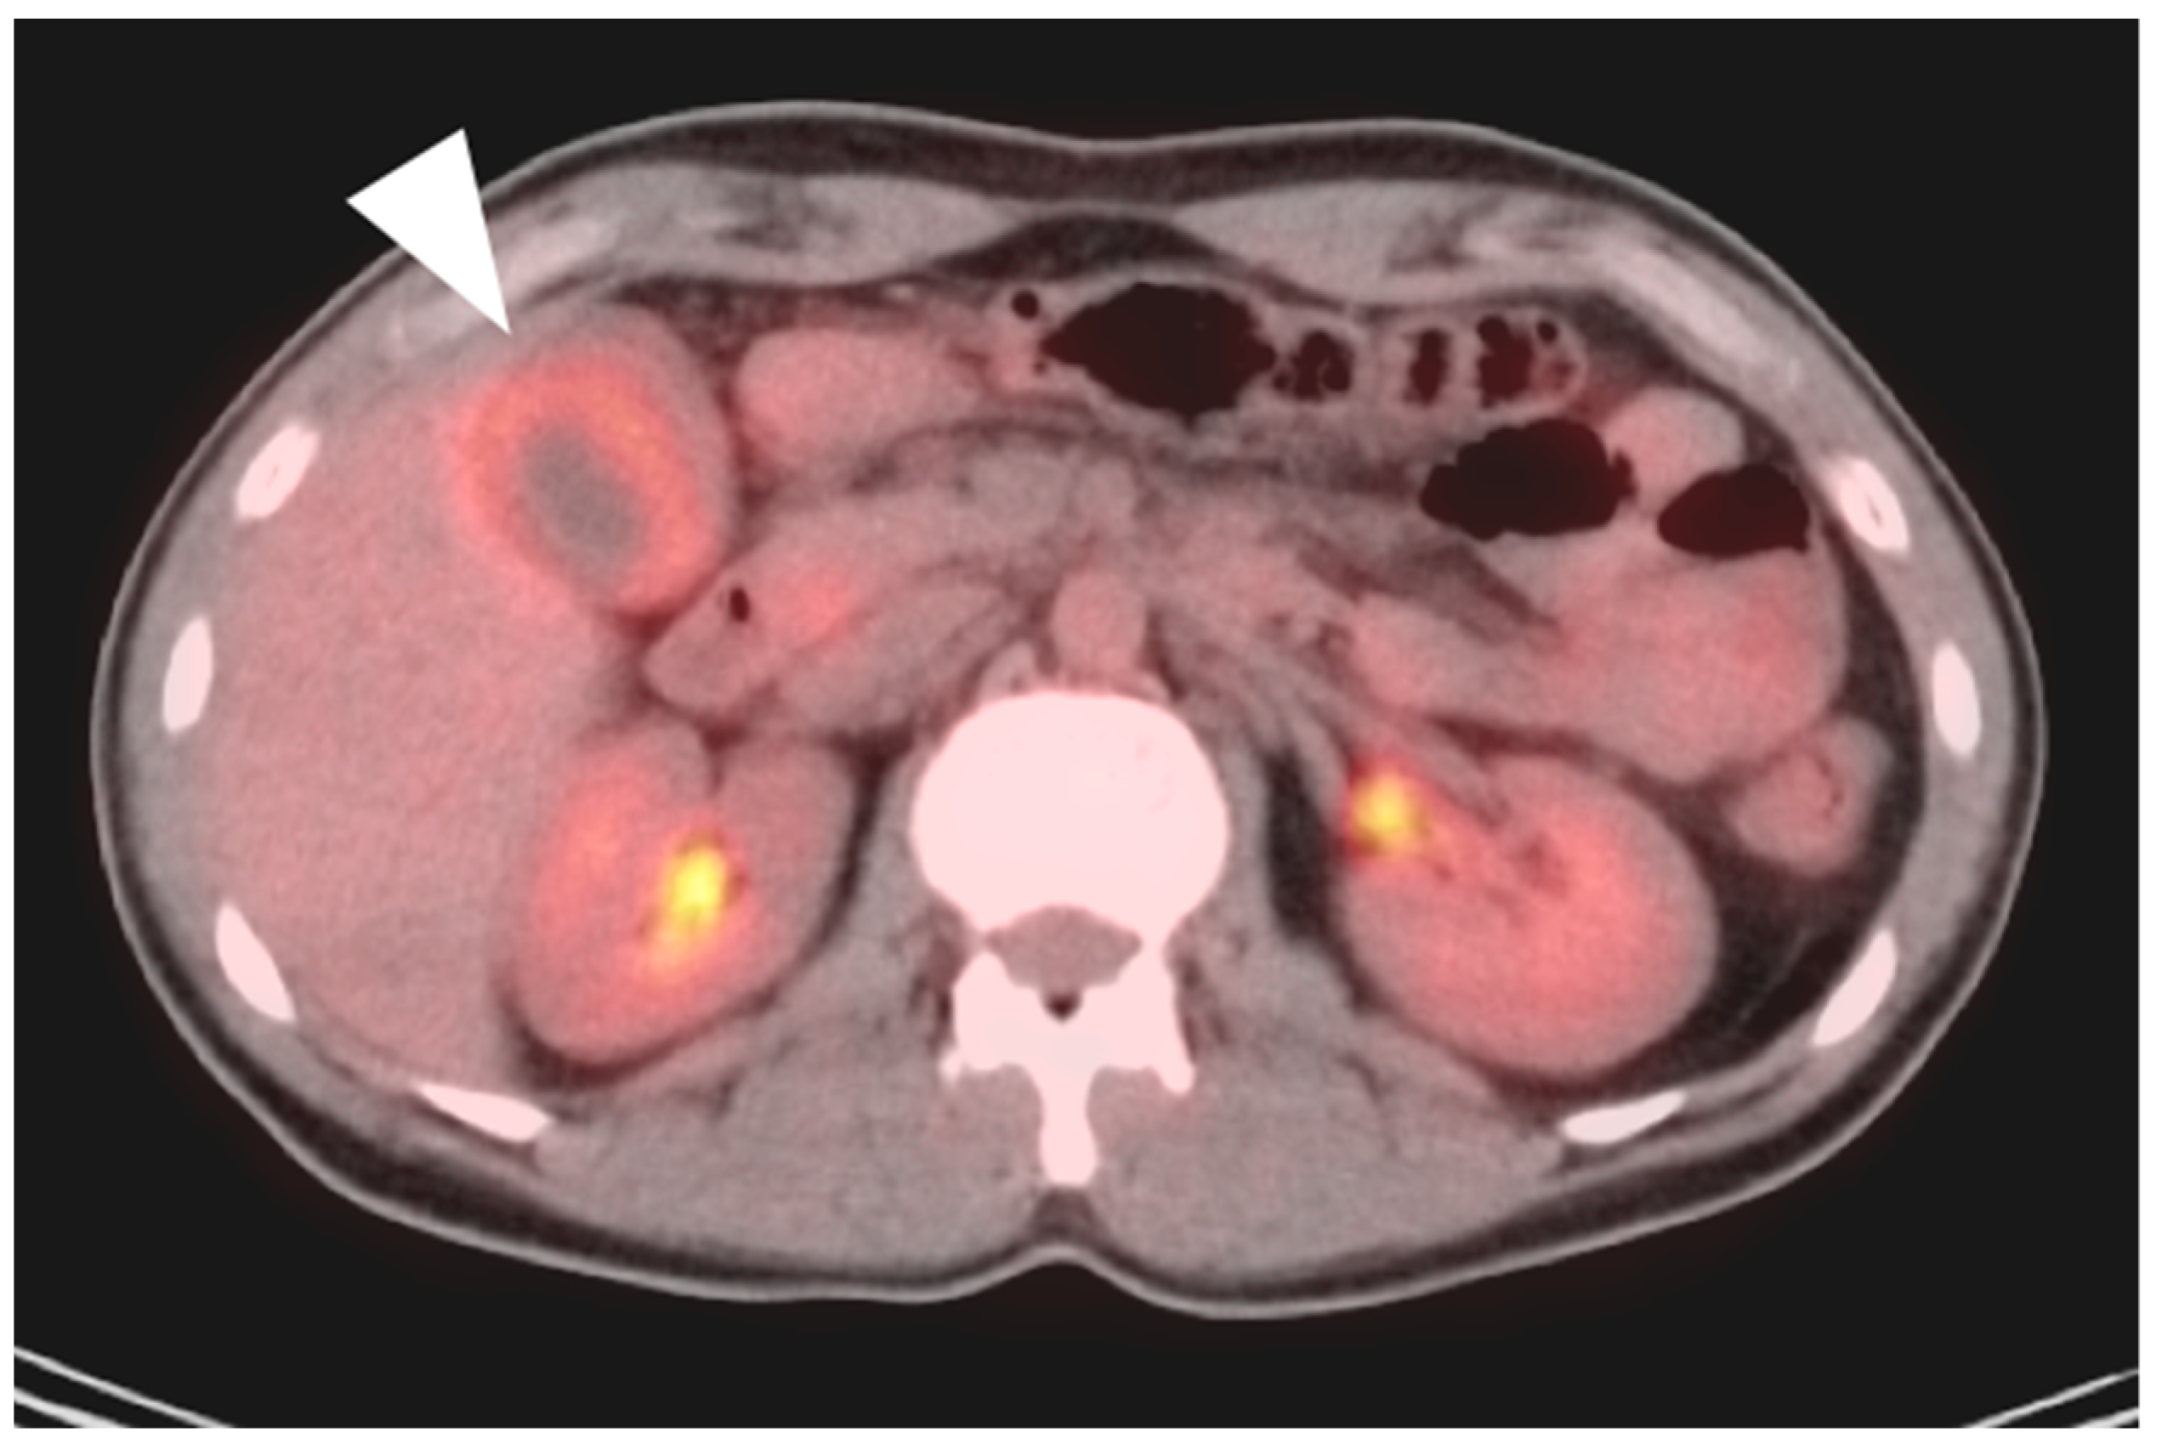

3. Gastrointestinal Stromal Tumor (GIST)